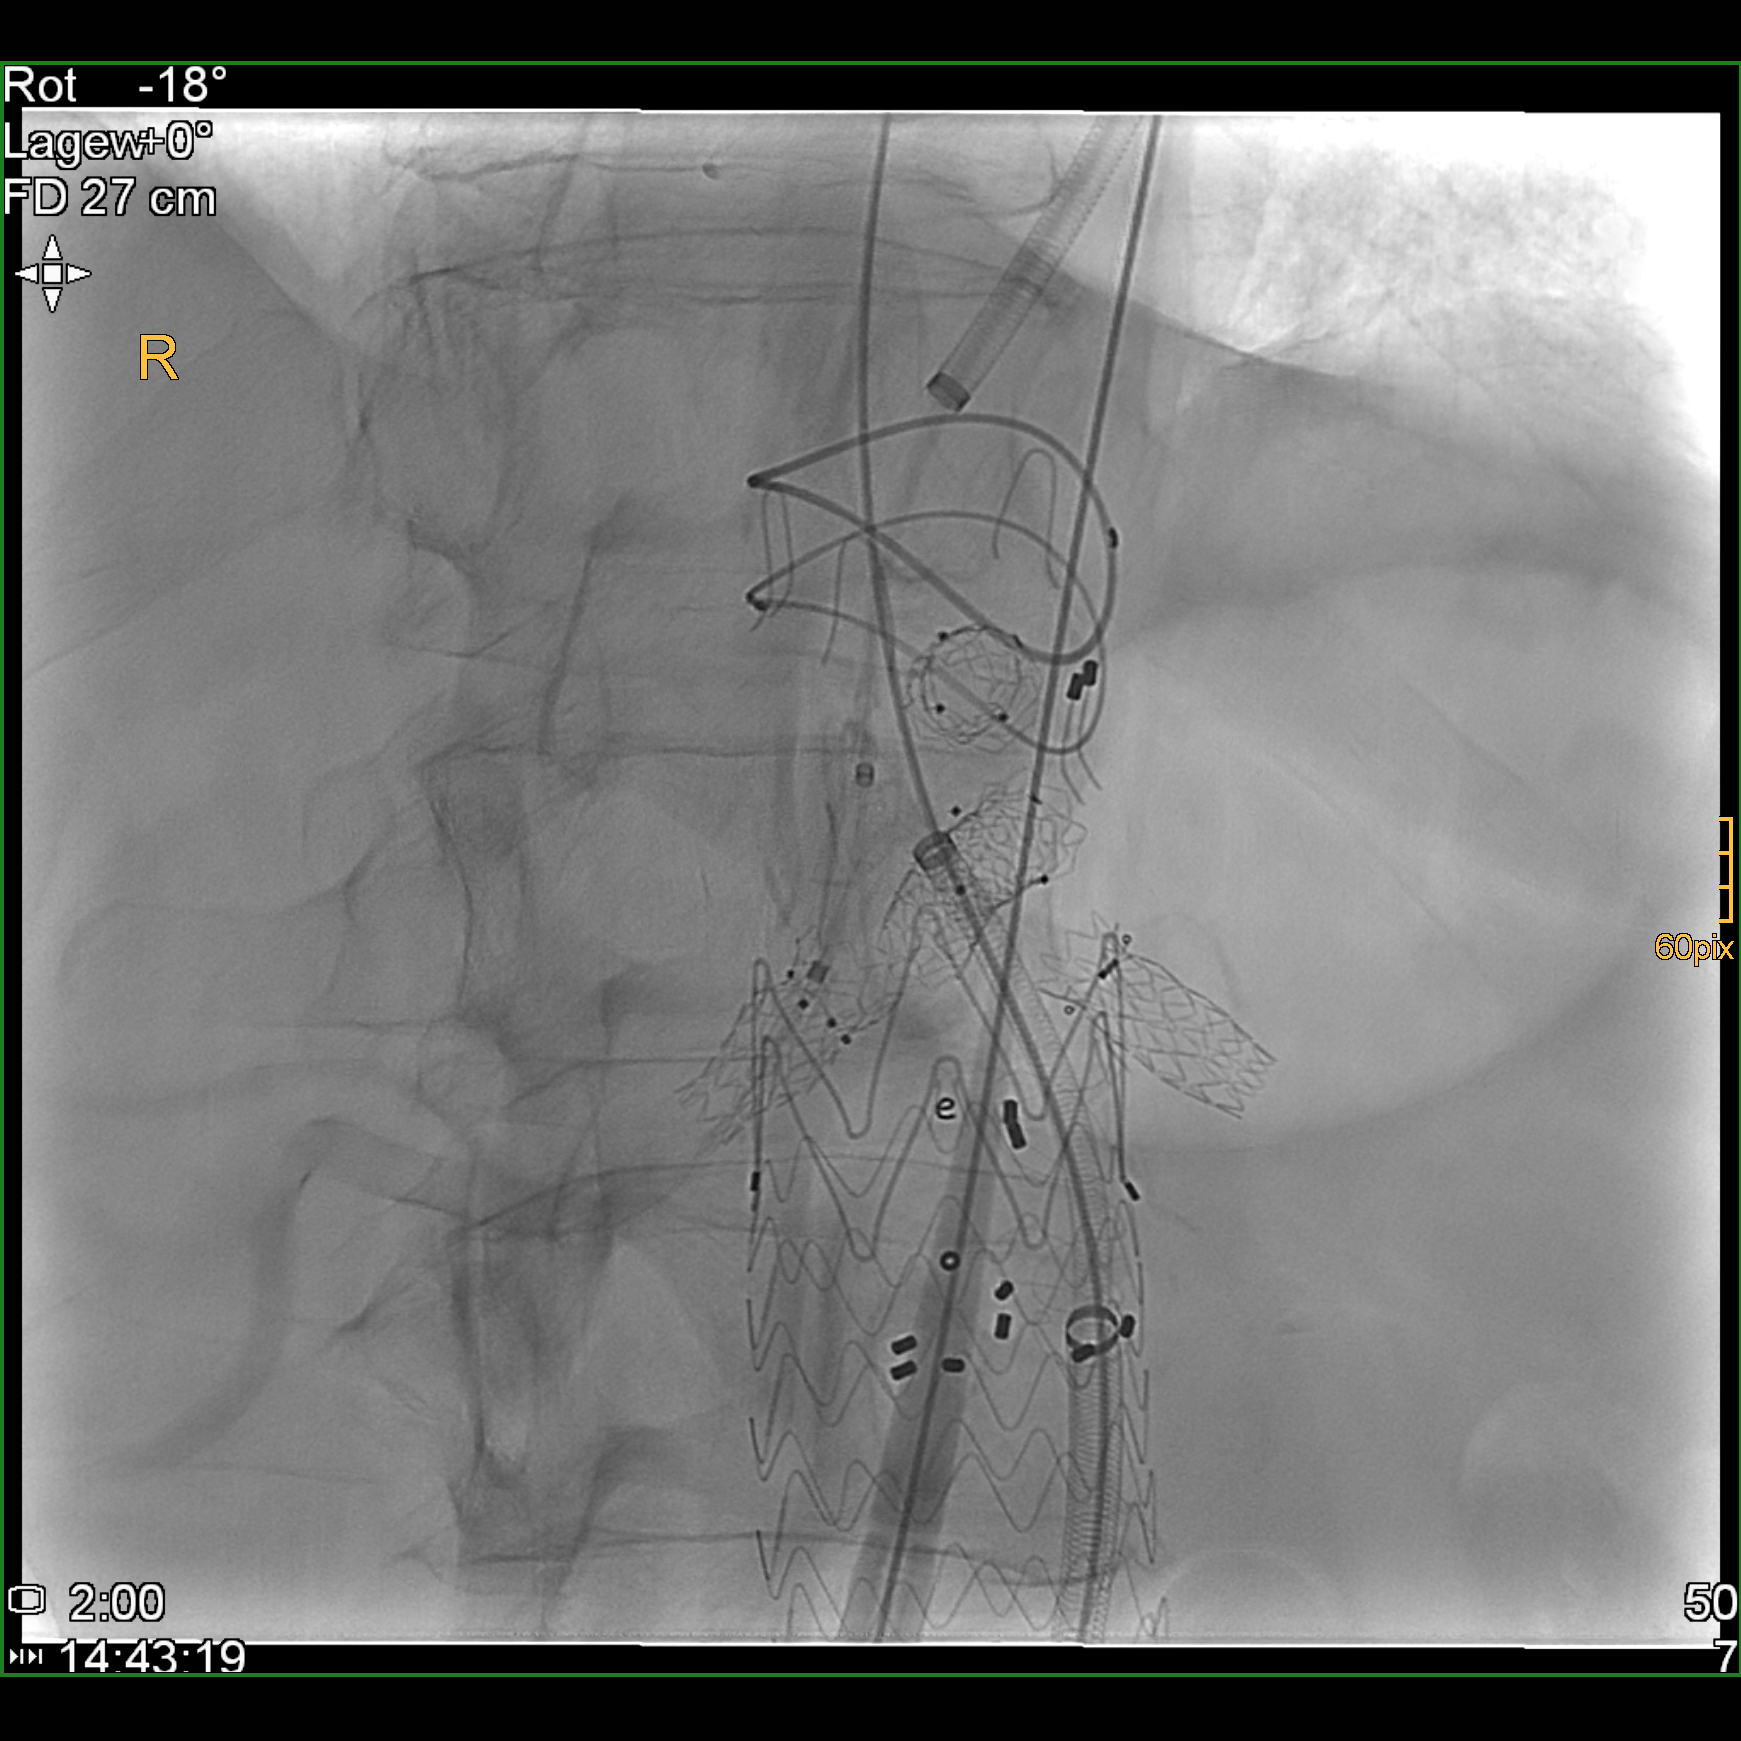

Nach Innsbruck kam Glodny aufgrund eines persönlichen Treffens mit o. Univ.-Prof. Dr. Werner Jaschke, dem Leiter der Innsbrucker Universitätsklinik für Radiologie. „Aus einem zunächst nur kurz angesetztem Termin bei ihm wurde ein mehrstündiges Gespräch, in dem ich erfahren habe, was hier in Innsbruck alles möglich ist und wie ich hier arbeiten kann“, erzählt Glodny rückblickend. Insbesondere die interventionelle Radiologie, durch die vielfältige therapeutische Eingriffe etwa in der Behandlung der arteriellen Verschlusskrankheit, oder von Blutungen oder Aneurysmen, von Tumoren- oder Metastasen möglich geworden sind, fasziniert den Radiologen und Forscher. „Mit durch Hochfrequenzstrom erzeugter Hitze, z. B. dem Verfahren der sogenannten Radiofrequenzablation, können Tumore oder Metastasen in Organen wie Leber, Niere oder Lunge behandelt werden. Die Vorteile dabei sind, dass ein oder mehrere Tumore extrem zielgenau und gründlich zerstört werden können, die ganze Prozedur aber für die PatientInnen sehr schonend ist. Die Absprache mit den behandelnden KollegInnen zur Erstellung eines individuellen interdisziplinären Behandlungskonzeptes für jede einzelne Patientin und jeden einzelnen Patienten garantiert die beste Versorgung.“ Am Standort Innsbruck schätzt Glodny vor allem das hohe fachliche Know How und gerät dabei nahezu ins Schwärmen: „Hier wird interventionelle Radiologie in absoluter Perfektion betrieben! Vor allem von Professor Reto Bale, der ein absoluter Experte auch in der Behandlung großer Tumore ist, kann ich sehr, sehr viel lernen. Darüber hinaus ist auch die Zusammenarbeit mit den KollegInnen aus der Universitätsklinik für Neuroradiologie unheimlich wertvoll und effektiv.“